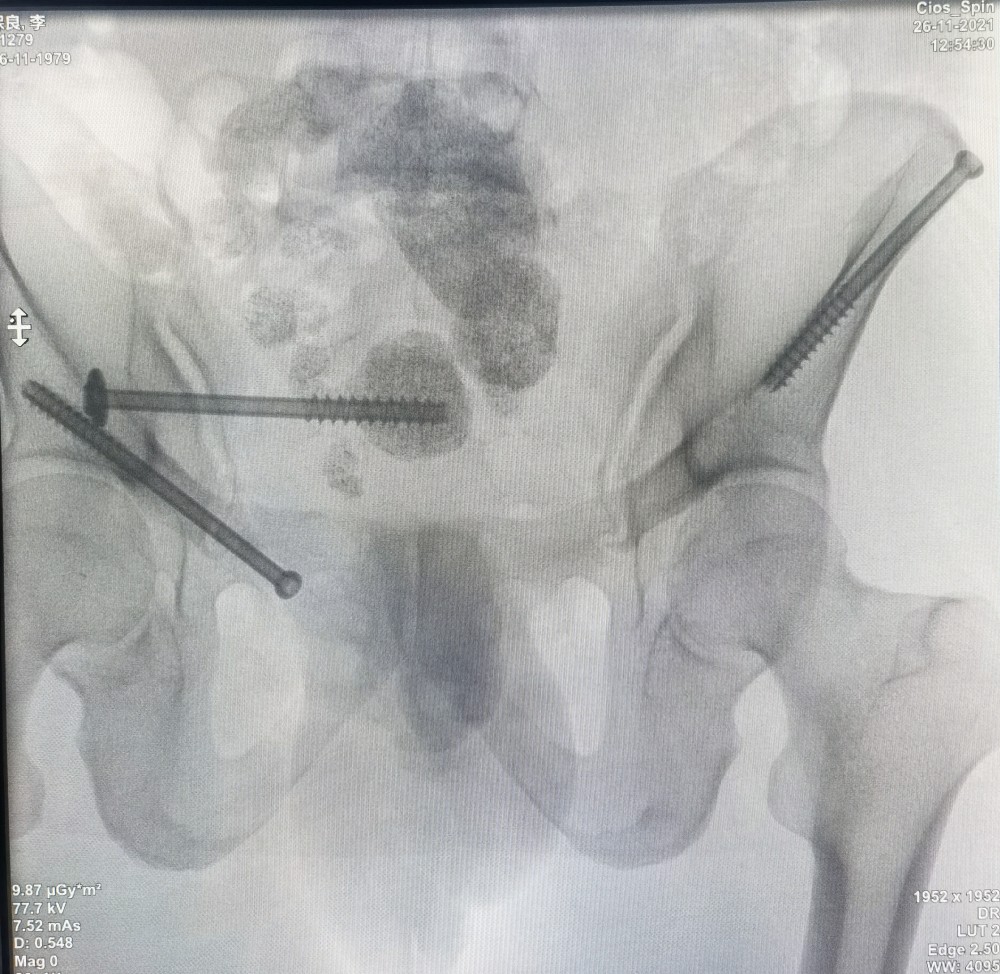

11月26日,91直播 创伤骨科中心贾燕飞教授团队完成自治区首例“天玑”Ⅱ骨科手术机器人辅助下经皮空心螺钉骨盆骨折内固定术。手术十分顺利,固定效果满意,仅仅开3个1cm的小切口,彻底解决问题。这是91直播 完成的首例也是自治区首例“天玑”Ⅱ骨科机器人辅助骨盆骨折手术,标志着91直播 复杂骨盆骨折的智能、精准、微创治疗达到了一个新的高度。

骨盆骨折被称为创伤骨科的“皇冠”,骨盆外观不规则,螺钉安全通道极为狭窄,手术难度高。术中经过C臂环扫后得到患者骨盆三维图像信息,经计算机模拟设计出最佳置钉方案,由机械臂精准引导植入各螺钉,术中出血仅15ml,切口长度不足1cm。真正做到了精准、微创治疗。